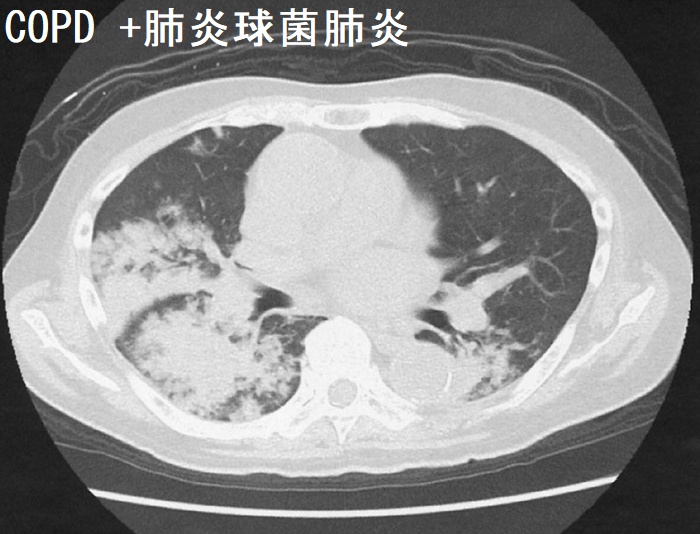

COPD患者は気道感染をおこしやすく、重症化する危険性は高いため、予防接種(23価肺炎球菌ワクチン、インフルエンザワクチン)が推奨されます。

COPD 急性増悪の治療は、ABC アプローチを行う

- A:Antibiotics(抗菌薬);肺炎球菌、モラクセラ菌、インフルエンザ桿菌などに有効な抗菌薬を選択

- B :Bronchodilators(気管支拡張薬)→ 吸入型短時間作用性β2刺激薬(SABA)+抗コリン薬

- C :Corticosteroids(ステロイド);抗炎症作用による粘液分泌・気管浮腫の改善。気管支拡張薬の反応性を高める

中枢性鎮咳薬で咳嗽を過剰に抑えると、排痰を阻害するため、安易な使用は控える。

ハイフローセラピー(高流量鼻カニュラ、ネーザルハイフロー)も追加。

COPD 患者は、肺炎などの呼吸器感染症をおこし呼吸不全(pH<7.35 もしくは PaCO2>45 mmHg)に陥る。まず呼吸管理を行うと同時に、喀痰Gram 染色をオーダー。人工呼吸器関連肺炎(VAP)による人工呼吸器依存を防ぐため、第一にNPPV(非侵襲的陽圧換気)が推奨されます。ただし、